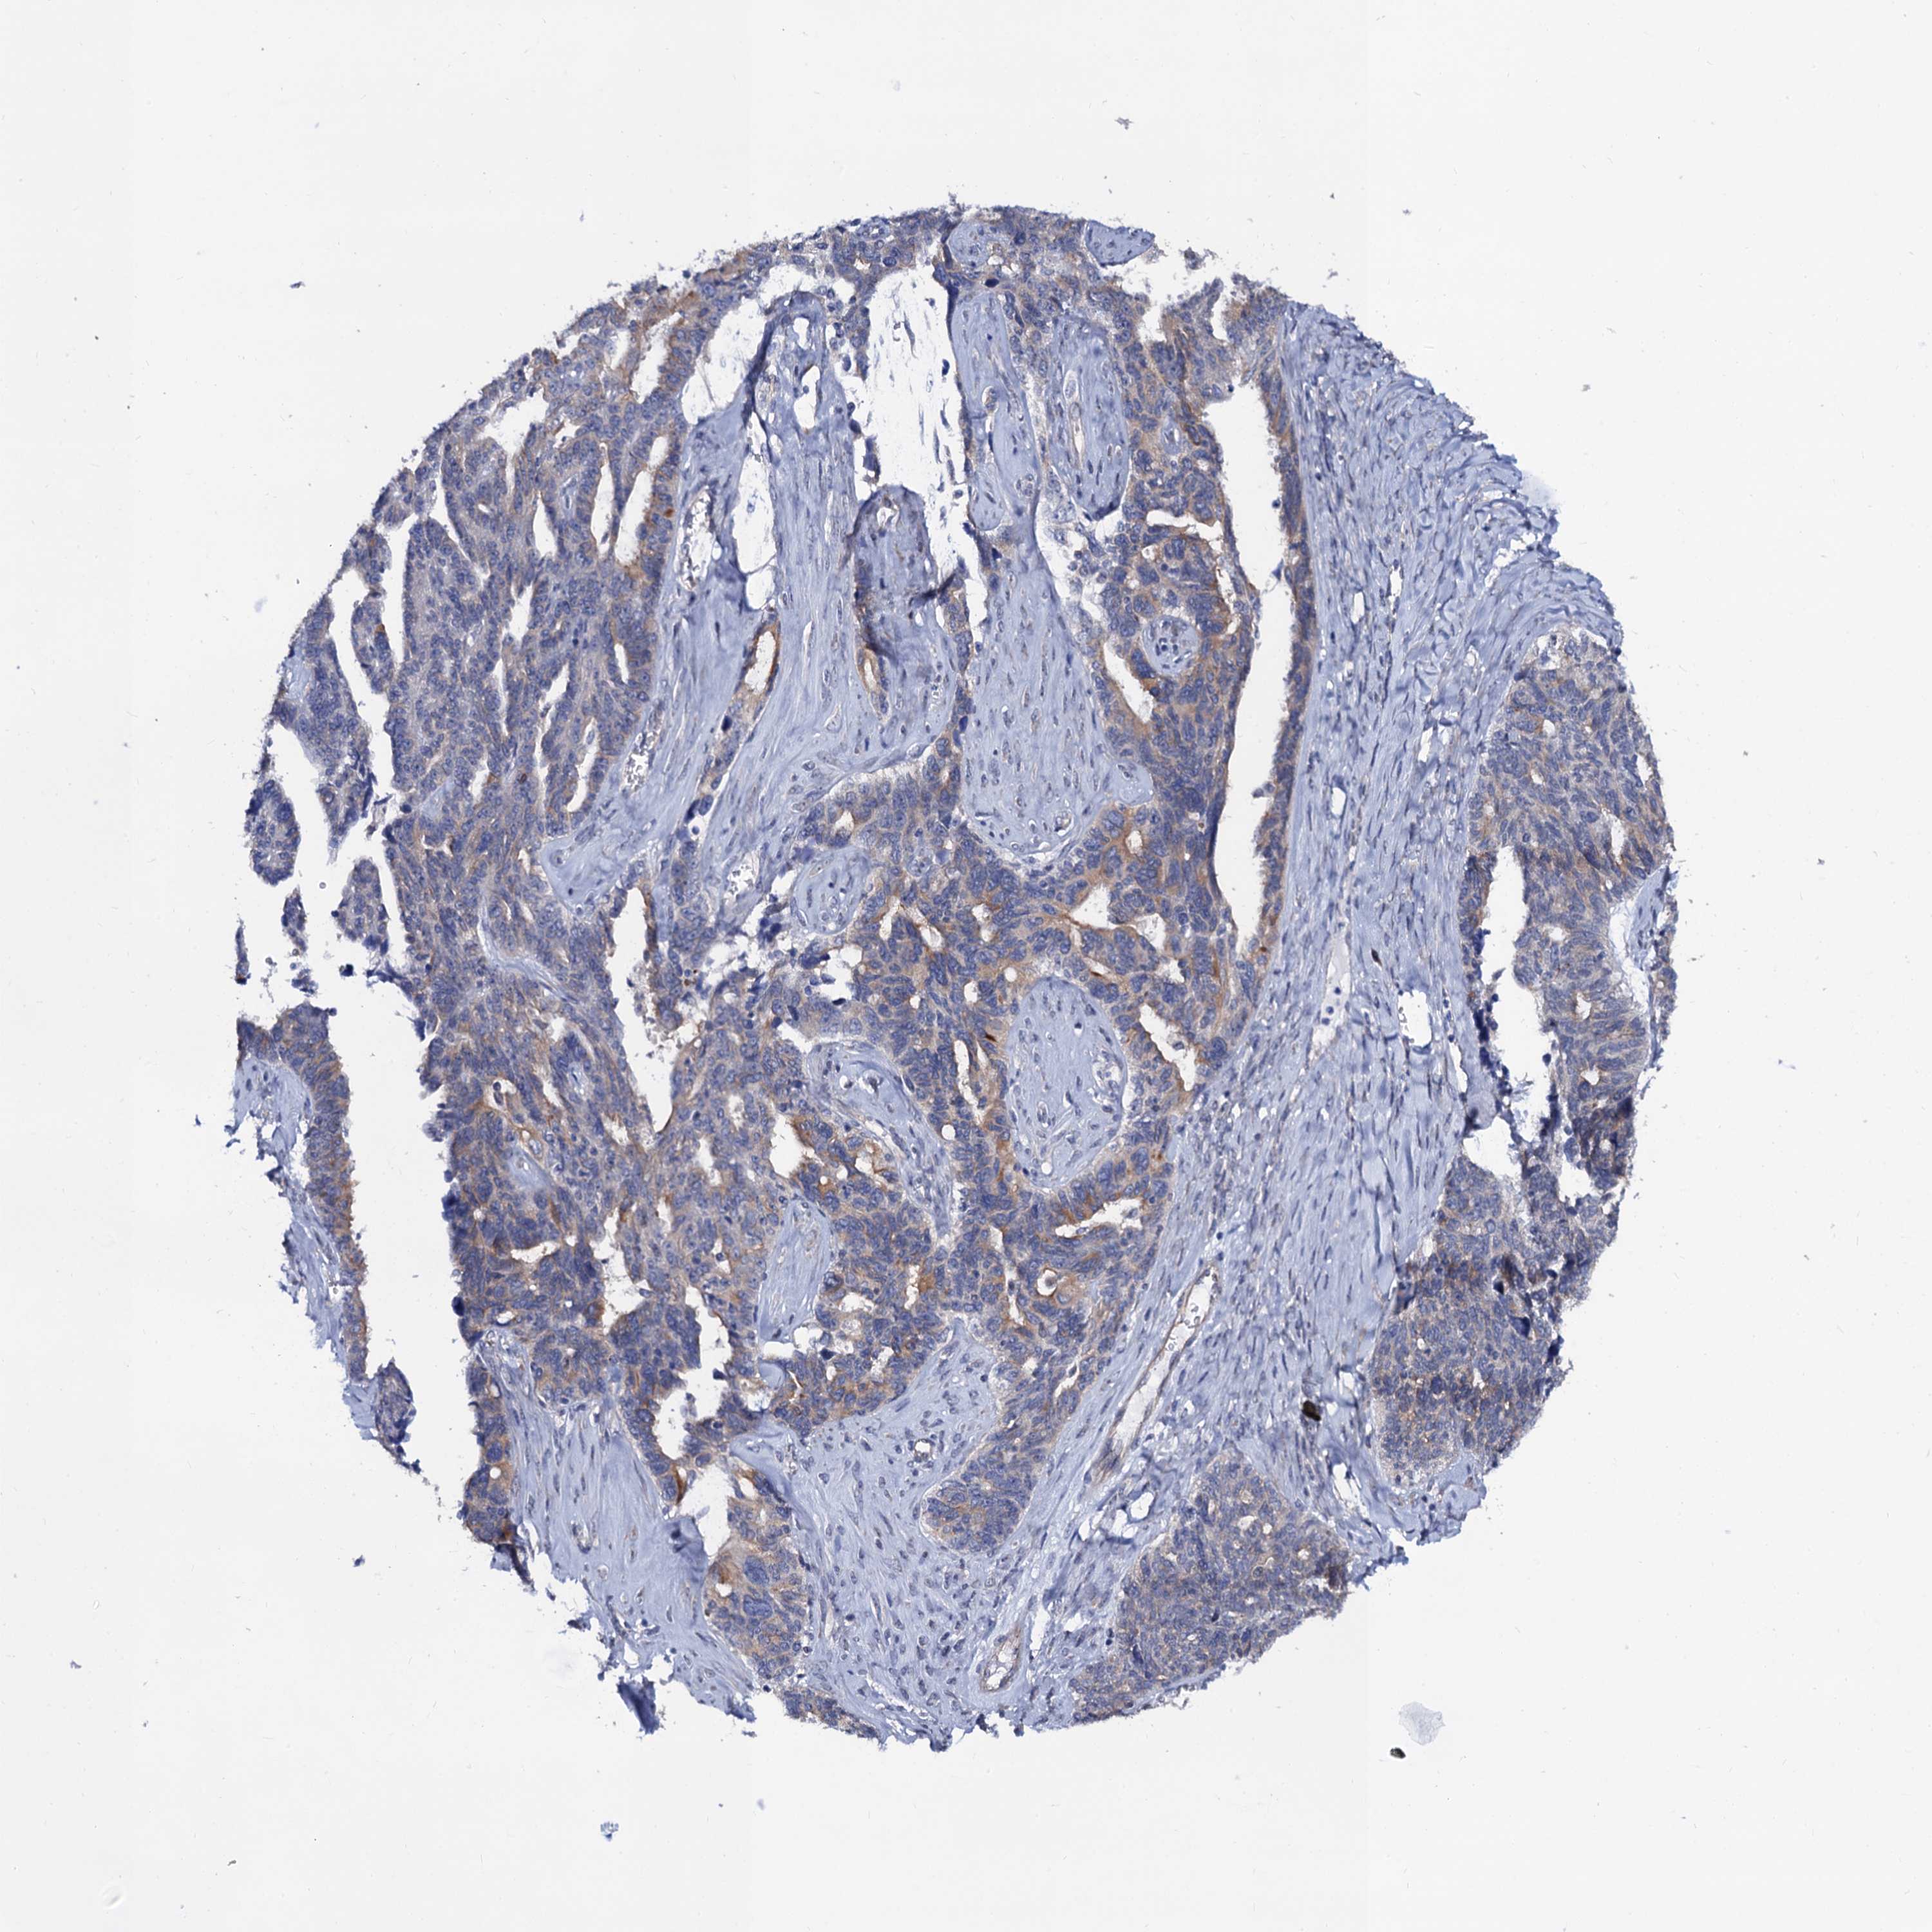

OVARIAN CANCER - Protein expressioni

A mouse-over function shows sample information and annotation data. Click on an image to view it in a full screen mode. Samples can be filtered based on level of antibody staining by selecting one or several of the following categories: high, medium, low and not detected. The assay and annotation is described here.

Note that samples used for immunohistochemistry by the Human Protein Atlas do not correspond to samples in the TCGA dataset.

Antibody stainingi

Antibody staining in the annotated cell types in the current human tissue is reported as not detected, low, medium, or high, based on conventional immunohistochemistry profiling in selected tissues. This score is based on the combination of the staining intensity and fraction of stained cells.

Each image is clickable and will lead to virtual microscopy that enables deeper exploration of all samples and also displays staining intensity scores, fraction scores and subcellular localization as well as patient and tissue information for each sample.

Antibody HPA040234

Staining

High

Medium

Low

Not detected

Intensity

Strong

Moderate

Weak

Negative

Quantity

>75%

75%-25%

<25%

None

Location

Nuclear

Cytoplasmic/membranous

Cytoplasmic/membranous,nuclear

Cystadenocarcinoma, serous, NOS

Carcinoma, endometroid

Cystadenocarcinoma, mucinous, NOS

Carcinoma, NOS